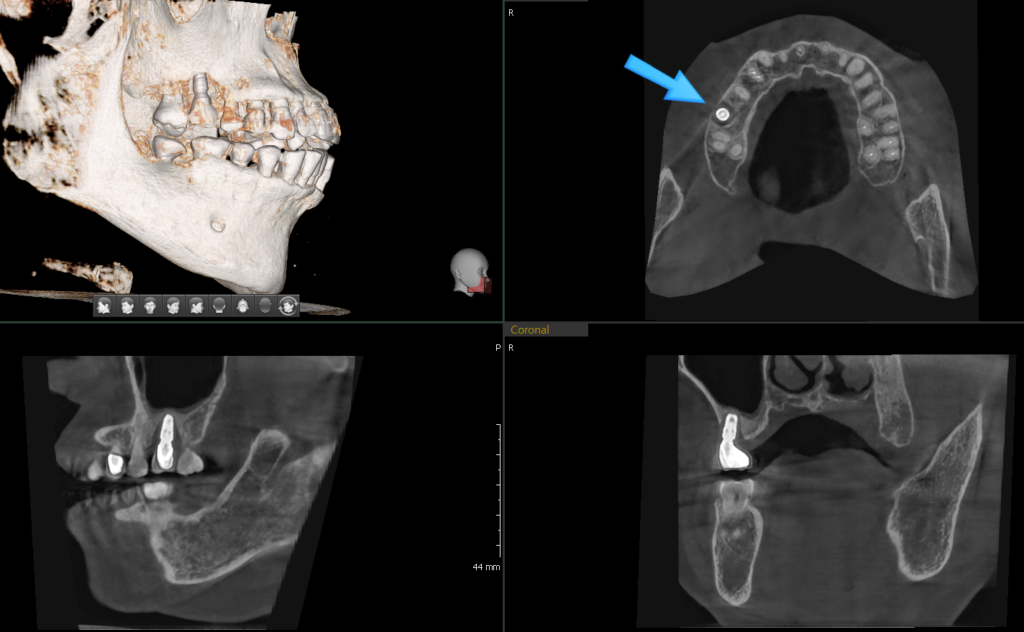

23. 02. 24(임플란트 뿌리 부분 주변으로 번져있는 염증)

혹시 빨간색 표시한 부위의 염증이 엑스레이에서 보이시나요? 임플란트의 나사선을 타고…잇몸뼈가 검게 바뀌어 있는 부분 말입니다. 엑스레이는 2D 영상이기에 바깥쪽과 안쪽이 중첩되어 염증의 소견이 전문가의 눈에서만 보입니다.

위의 경우 엑스레이 상으로 이정도의 수직적 골파괴가 확인 되었다면 조금 더 확실한 확인을 위해 컴퓨터 단층 촬영 CT를 해보게 됩니다.